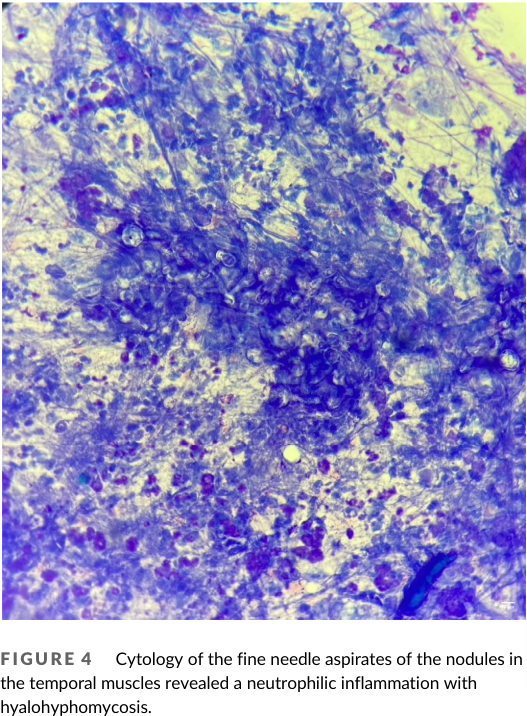

칸디다는 곰팡이성 질환으로 보통 거론되는 게 에이즈 환자등, 면역계가 무너진 환자에서 이차적 기회감염에 해당하는 부분이다. 개에서도 마찬가지로 대부분 면역 억제 치료를 받을 때 주로 증상이 나타날 수 있는데 이번 증례는 뇌에 감염이 있을 때의 증례, 특히 MRI 촬영과 부검을 통한 재확인이 매우 가치 있는 논문이라 하겠다.